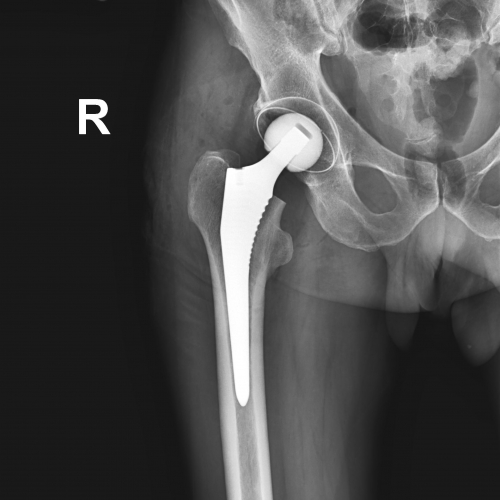

Эндопротезирование тазобедренного сустава